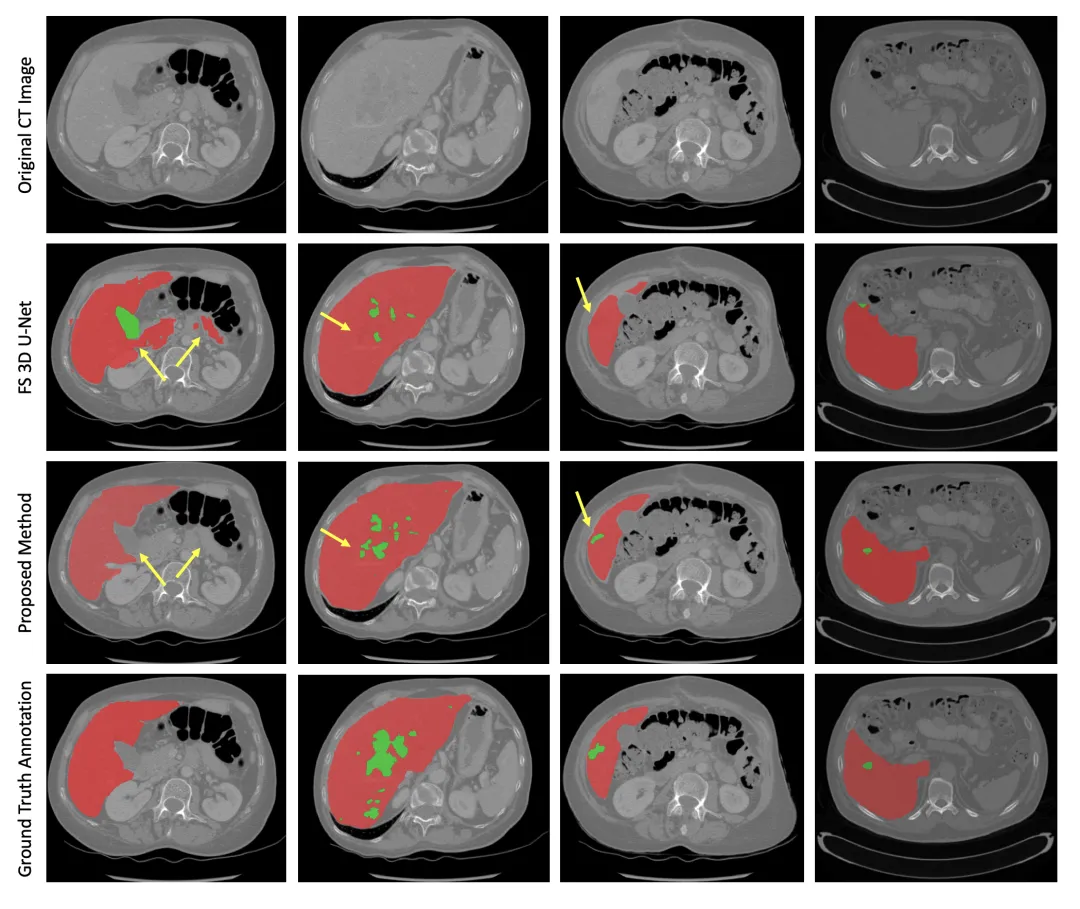

视觉与定量结果一致:可视化结果显示,所提方法的分割结果与真实标注高度吻合,尤其在细小肿瘤和复杂边界的处理上表现优异,3D重建体积平滑且解剖结构合理,符合手术规划与定量评估的临床需求。

图3:代表性案例的分割结果可视化对比